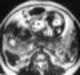

Dilated bladder

Urinary retention is an inability to completely empty the bladder. Onset can be sudden or gradual. [Source: Wikipedia ]